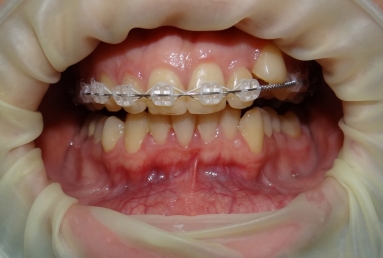

SAPPHIRE ORTHODONTIC DEVICE

Orthodontic treatment, external sinus lifting, dental implant and zirconium crown.